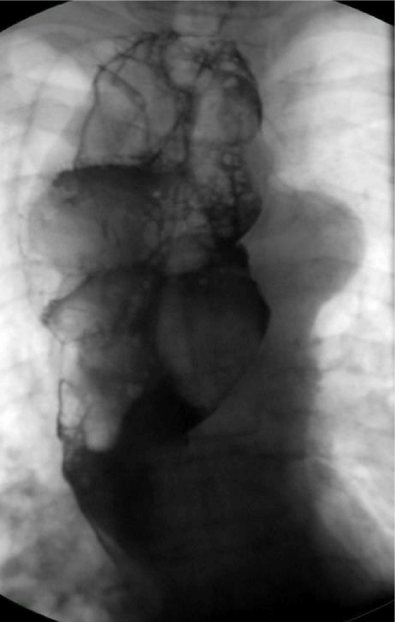

A cine-esophagogram showed a dilated esophagus with a large, irregularly circumscribed contrast media filling defect mainly throughout the upper two-thirds of esophagus (Figure 5).

Figure 5: Cine esophagography: dilated esophagus with large contrast media filling defect througout the esophagus.